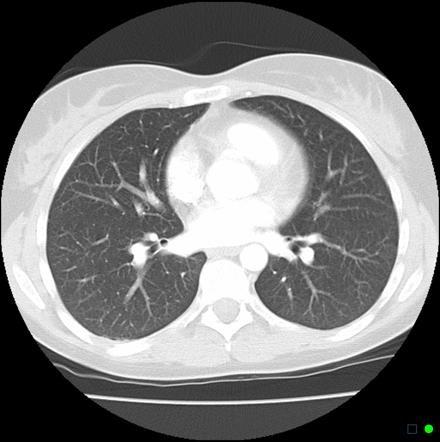

This would be a CT scan of your lungs, as compared to normal ones.